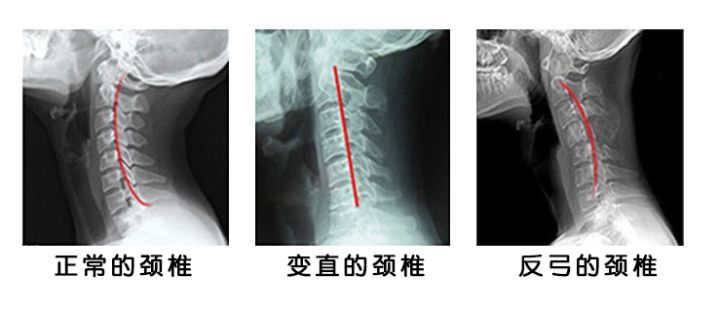

我们看看人体的颈椎构造图,正常的颈椎其实是向后凹形的,长期的低头久坐彝族,颈椎会向前倾,才开始是变直,严重患者是往里面倾斜,颈椎不好的人主要是由于工作原因,学习原因,或者长期久坐造成的,一旦不重视就会发生第三张图那种反弓的情况,重点说一下:很多严重患者睡觉居然不睡枕头,不睡枕头不行的,至少垫1个最矮的薄片让颈椎有支撑才可以,如果长期不睡枕头颈椎很难复原的